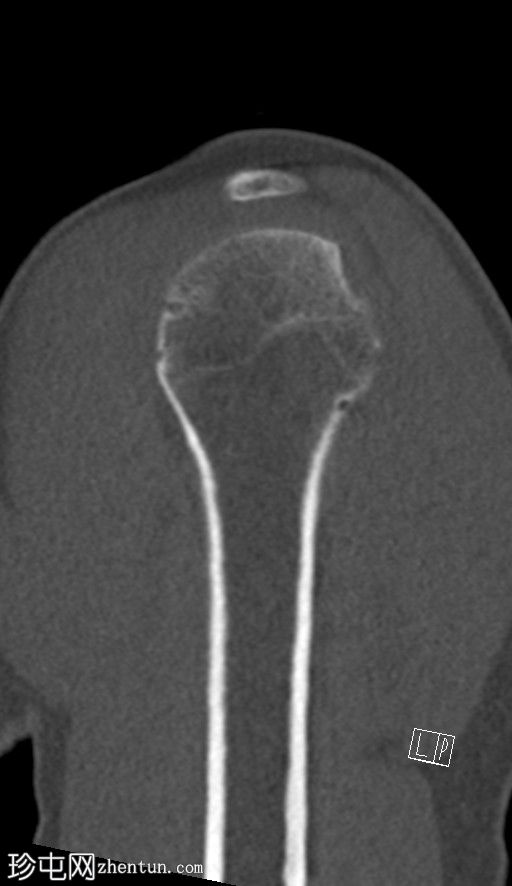

冠状位

非增强

CT显示肱骨头后外侧缘存在缺损及骨碎片,提示Hill-Sachs损伤。

右侧肩胛盂前下缘可见一小块骨碎片,提示Bankart损伤。